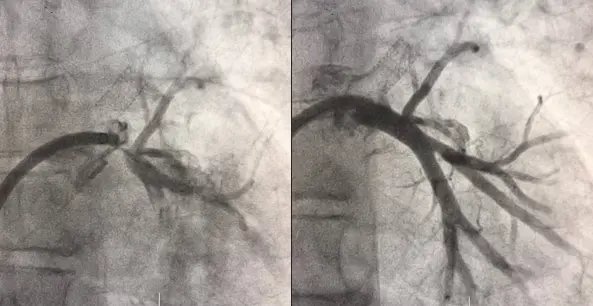

Рисунок 3. Левая нижняя легочная вена до и после стентирования.

Вмешательство проводилось через бедренный венозный доступ под местной анестезией. Основная сложность операции заключалась в полной окклюзии обеих легочных вен и необходимости точной навигации инструментов в условиях ограниченной визуализации. После реканализации поражённых участков были имплантированы стенты, обеспечившие надёжное восстановление просвета сосудов и полноценный венозный отток из лёгких.

В результате кровоток по левой верхней и левой нижней легочным венам полностью восстановлен. Состояние пациента стабилизировалось, одышка регрессировала. В настоящее время пациент чувствует себя хорошо.